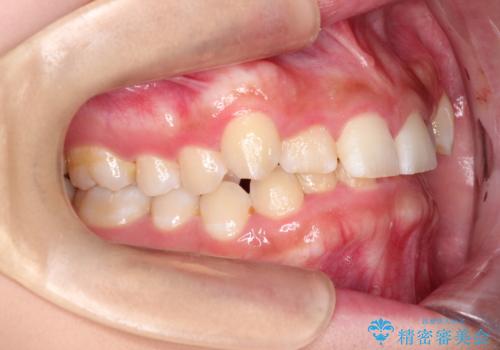

- 前歯の凸凹と深い噛み合わせを主訴に来院されました。

下の前歯が見えないほどのディープバイト症例でした。

ワイヤー矯正にて下顎前歯の圧下と臼歯部の挺出を効率的に行うことができました。